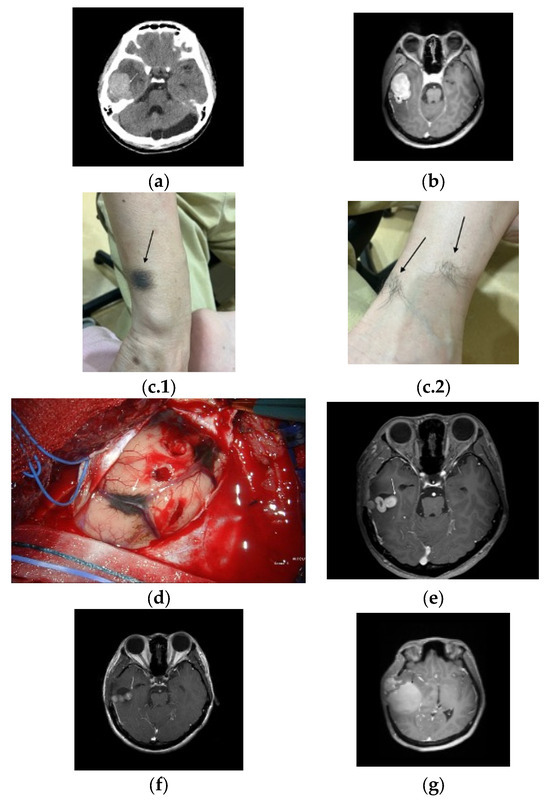

2. Detailed Case Description